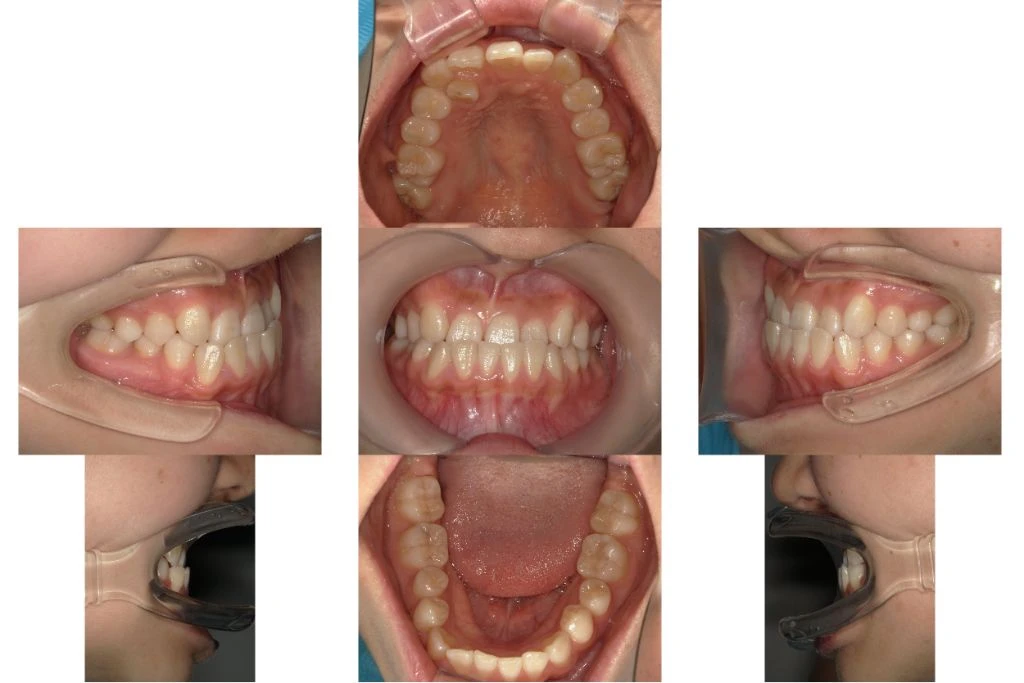

【治療前】

セファロ分析から、明らかに上顎劣成長及び下顎骨の過成長を認めます。MSEの適用症例と判断しました。

【治療後】

MSEを併用しながらワイヤー矯正が終了した状態です。本来の顎位で上下の正中(真ん中)が合ってきて概ね矯正治療としてのゴールが見えてきました。

【患者情報】

- 年齢:23歳

- 性別:女性

- 方法:表側セルフライゲーションブラケット(Empower)+シルバーワイヤー+MSE+下顎遠心移動用アンカー2本

- 回数:1回/月

- 動的期間:2年